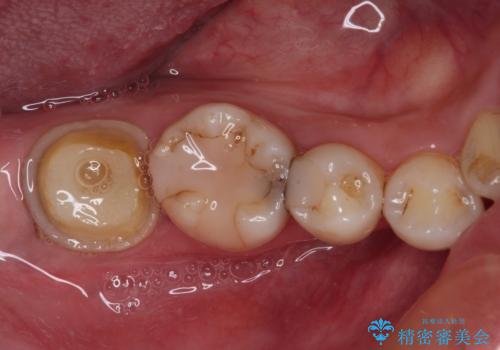

- かかりつけ医にて、歯の高さが不足しているためセラミッククラウンの装着はできないと言われたとのことで来院された患者様です。

診察したところ、確かに歯の高さは不足していましたが、土台の立て直しや歯の削り方を調整することでオールセラミッククラウンでも補綴可能と思われました。

ただし、クラウンの厚みは極力薄くした方が維持力が増すため、高強度のフルジルコニアクラウンにて補綴治療することとしました。